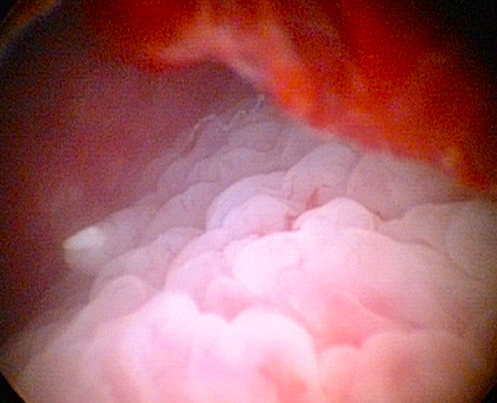

The hysteroscope is used to examine in detail the uterine cavity.

This white patch is cancer of the lining of the uterus. (endometrial cancer)